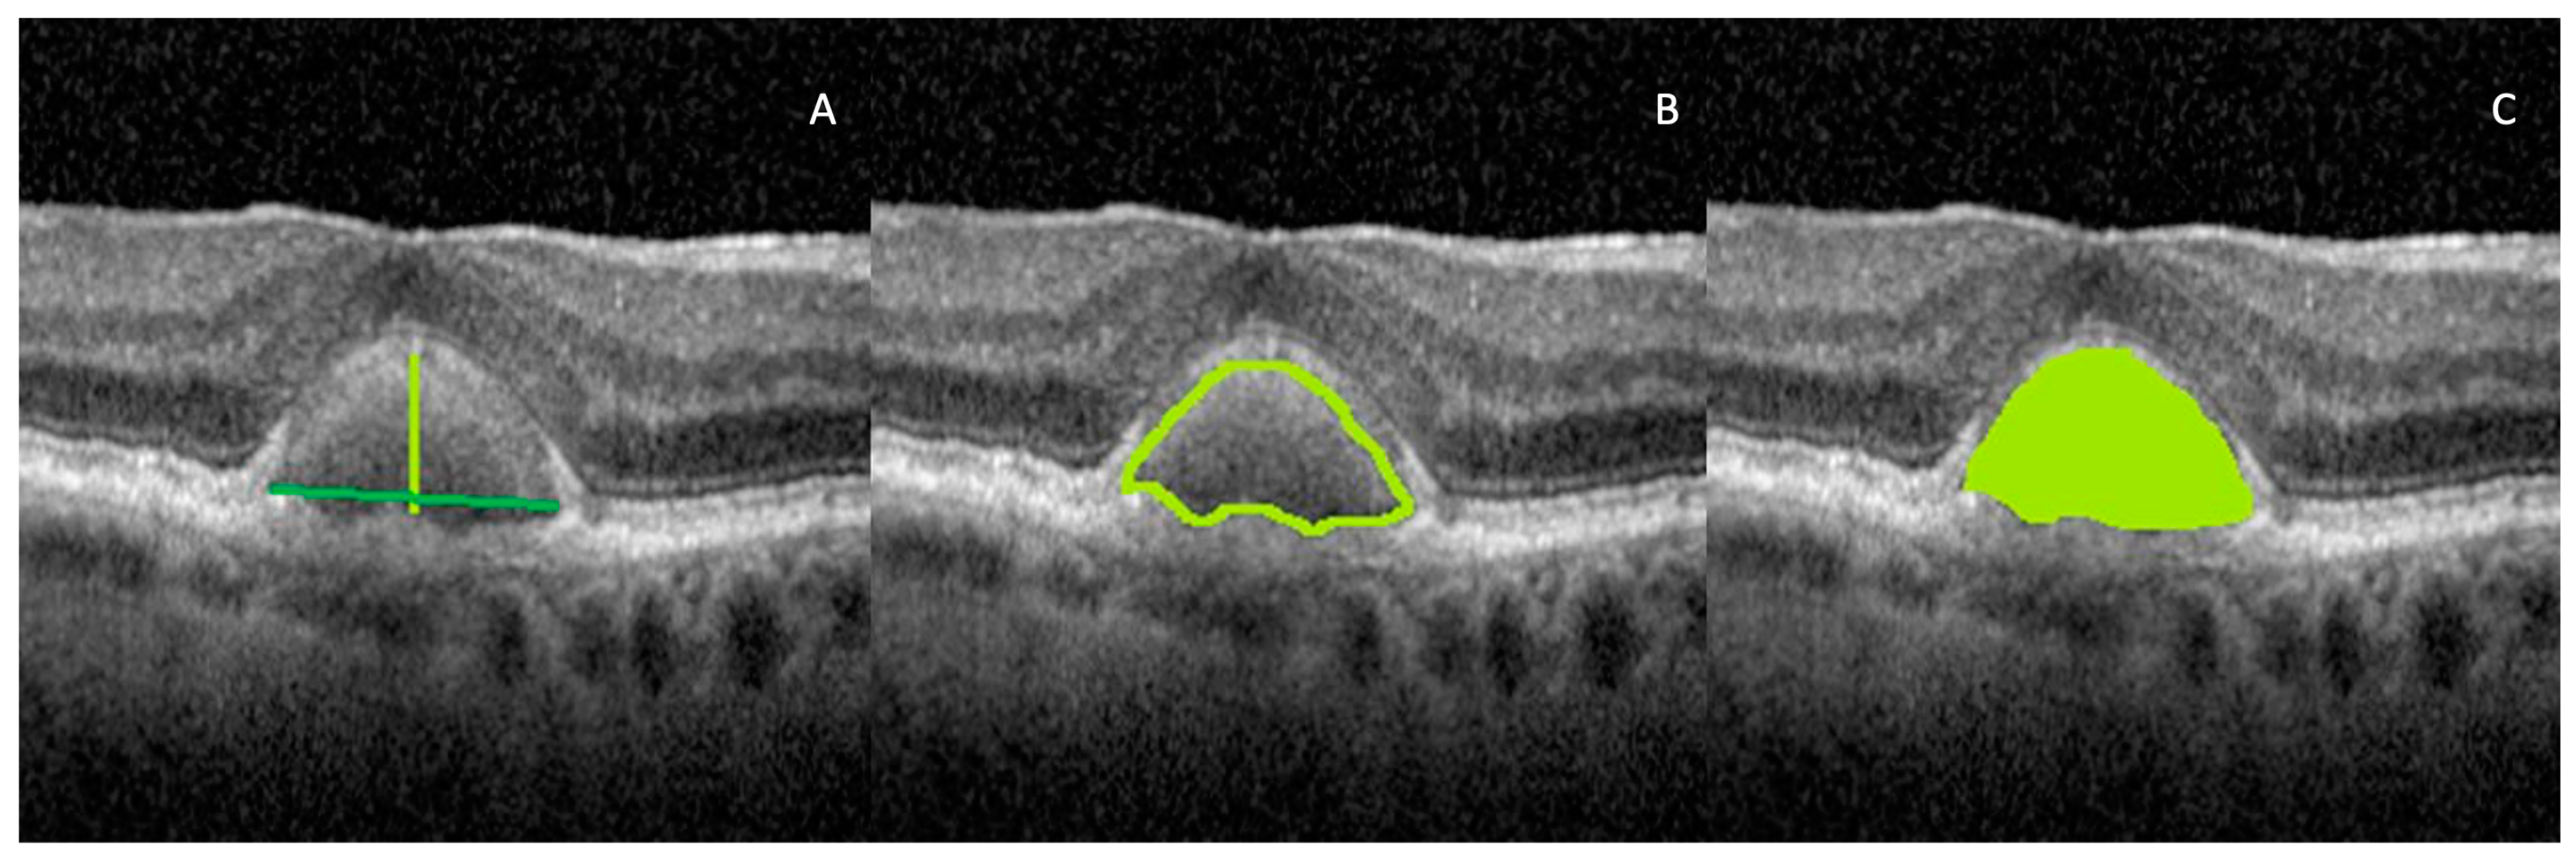

Images were analyzed using the public domain software, Fiji (version 1.53T, https://imagej.nih.gov/ij/ (accessed on 20 March 2022) [16]. Before uploading the OCT images to ImageJ, the vertical-to-horizontal ratio of the image was changed to 1:1 µm. We analyzed the non-stretched OCT scans to overcome the erroneous quantification of parameters [17]. First, the OCT image was opened in Fiji software and the scale was set. We measured a pixel length of 200 µm as given on the scale at the bottom of the OCT scan image, using the line tool. We further used the “magnifying glass” at 400% to obtain a better view of the vitelliform lesion and to easily identify its margins. With the help of the “polygon selection tool”, only the region with the vitelliform lesion was selected using the “crop button”. As previously defined by other authors, the anterior AVL boundary was considered the external limiting membrane, while the posterior AVL boundary was the retinal pigment epithelium–(basal lamina)–Bruch membrane (RPE–(BL)–BrM(RPE+BL–BrM)) complex [5]. If a PED was found, the posterior boundary was the RPE–BL. For each eye, we analyzed all the scans passing through the AVL and we chose the one passing through the fovea. On this particular scan, using the “straight line” option, we drew the base width and the maximum height of the vitelliform lesion. Using the “freehand line” tool we selected the entire vitelliform lesion to measure its perimeter. We performed 3 measurements for every parameter/eye and averaged them. The parameters are classified as follows:

2.4.1. Vitelliform Lesion Size

• Maximum height: defined as the distance between the apex of the lesion and the RPE (see Figure 2. A: light green line). We defined apex as the vertex located at the highest point of the AVL or the point furthest from the base.

• Base width: defined as the distance between either edge of the lesion (see Figure 2A: dark green line).

Using the “freehand line” tool, the vitelliform lesion was delineated; this represents the region of interest (ROI) that was added to the ROI manager. If the AVLs were located on top of a drusenoid PED, we did not include the PED in the measurements. We set the needed measurements such as area and density characteristics, and then we pressed the measure button. We further extracted the results.

c

Perimeter: defined as the total length of the vitelliform lesion outside the boundary (see Figure 2B).

d

Area (A) (1): defined as the sum of the areas of each individual pixel, ap, in calibrated square units, within the borders of the lesion (see Figure 2C):

A = a p ,

After the vitelliform lesion was delineated with the “freehand line” tool, we further analyzed various vitelliform lesion characteristics, as follows.

Figure 2. OCT images illustrating vitelliform lesion size parameters. (A) Maximum height (green light line) and base width (dark green line); (B) perimeter; (C) area. The stretched 1 × 1 pixel image was used for illustrative purposes only, to help visualize the details of the retinal structures.

Biomedicines 11 01382 g002